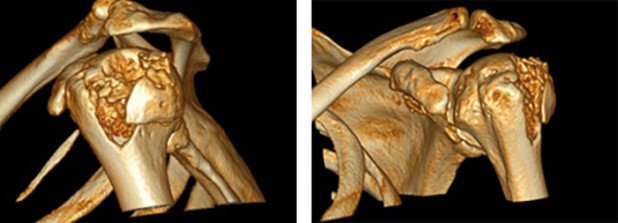

Weiterreichende Bildgebung wie Computertomografie

Eine weiterreichende Bildgebung wie die Computertomografie inklusive 3-D-Rekonstruktion kommt in der Regel dann zum Einsatz, wenn es darum geht zu entscheiden, ob die knöcherne Verletzung konservativ oder operativ behandelt werden soll.